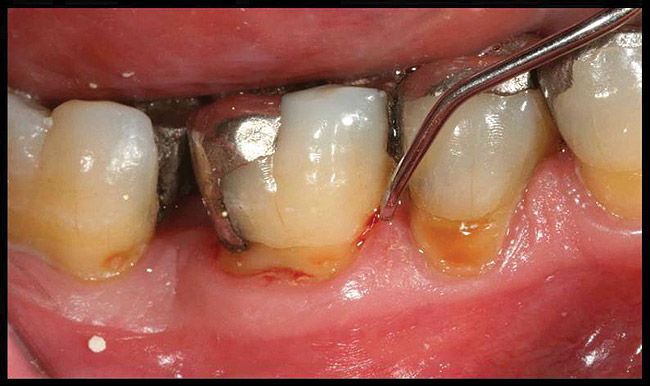

Locally delivered, controlled-release agents are a popular treatment adjunct and serve to augment scaling and root planing to help improve outcomes. Clinical studies have shown that use of such agents can provide an average of 0.5-mm additional pocket depth reduction over scaling and root planing alone, so the practitioner must weigh the cost-benefit ratio of using these products in each patient situation.39,40 A guideline for the appropriate use of locally delivered antimicrobials has been provided by the American Academy of Periodontology.41 These materials are contraindicated in patients with (1) multiple 5-mm pocket depths in one quadrant; (2) anatomic defects caused by periodontal diseases (intrabony defects); and (3) when the previous use of locally delivered agents has failed to control disease. As noted before, a follow-up reevaluation always should be completed to evaluate the success of any therapeutic intervention, generally at 4 to 6 weeks after treatment has been rendered30,31 (Figure 3A through Figure 3D).

Figure 3a   patient in posttreatment periodontal maintenance program returned with (A) isolated bleeding on probing;

Figure 3a

Figure 3b   patient in posttreatment periodontal maintenance program returned with (B) a 5-mm probing depth noted at a maintenance visit.

Figure 3b

Figure 3c  The site was treated by localized scaling and root planing, followed by use of Arestin (minocycline microspheres).

Figure 3c

Figure 3d  The resolution of inflammation and bleeding on probing on the reevaluation appointment 6 weeks later.

Figure 3d